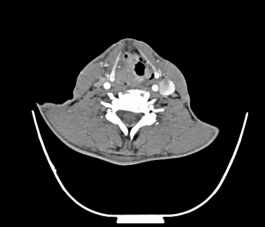

鼻咽癌发生颈淋巴结转移的概率最高,约占60%,很多患者以颈部肿块为首发症状,鼻咽癌的颈部淋巴结转移位置常常在颈深上淋巴结(大概说就是我们耳垂下方区域)。

常见的还有口咽、口腔、鼻腔鼻窦癌颈淋巴结转移、甲状腺癌颈淋巴结转移等。颈部恶性肿瘤的诊断需要借助详细的病史、全面的体格检查及辅助检查(包括彩超、CT、电子鼻咽喉镜等),最重要的还是要去耳鼻咽喉头颈外科专科就诊。